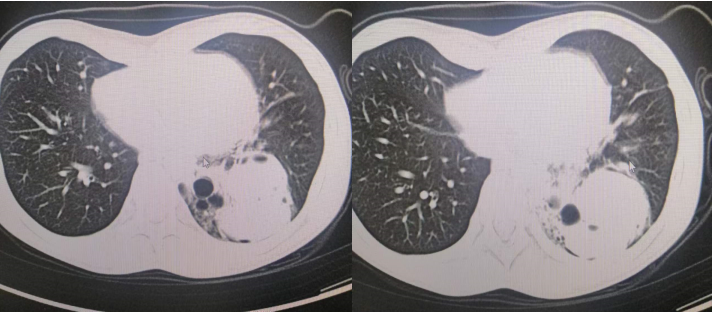

胸部CT:左下肺见斑片状及团块状混杂密度影,其内可见液平,边界欠清,局部支气管扩张;心包见积液影,左侧胸腔见少量积液影。

诊断意见:左下肺炎,左下肺脓肿待排,左侧胸腔少量积液,心包积液(如下图3和图4)。

图3-4 患儿胸部CT及检查所见